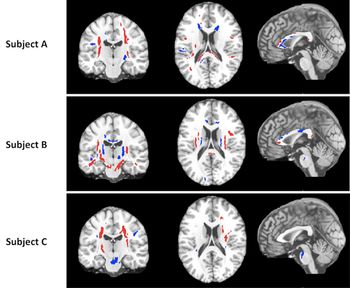

CHICAGO - Brain maps created with multiple MRIs reveal that Alzheimer’s disease affects men and women’s brains differently.